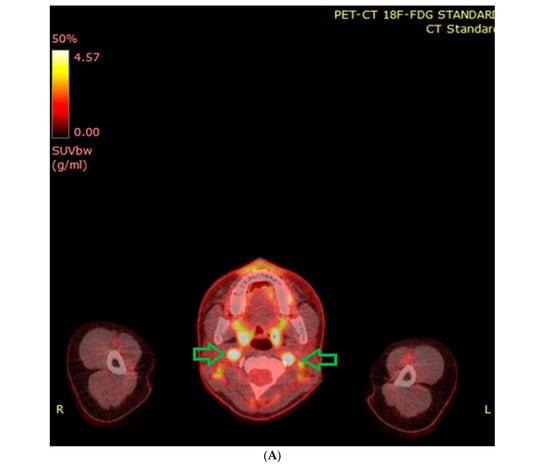

6.2. Functional Imaging